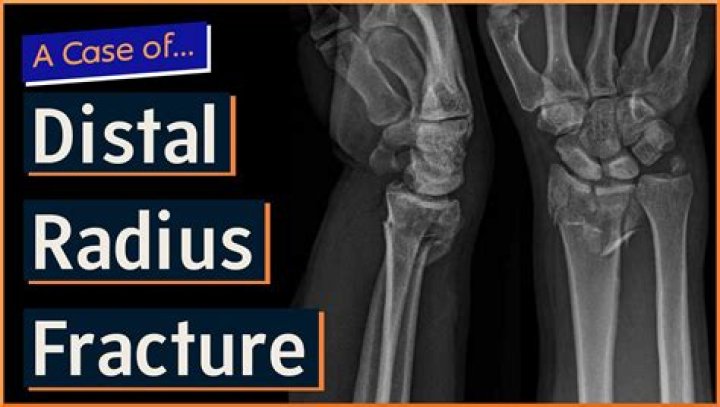

How do you rehab a distal radius fracture?

Rehabilitation of distal radius fractures is divided into 3 stages: splinting (for edema control), mobilization, and strengthening. With appropriate rehab...